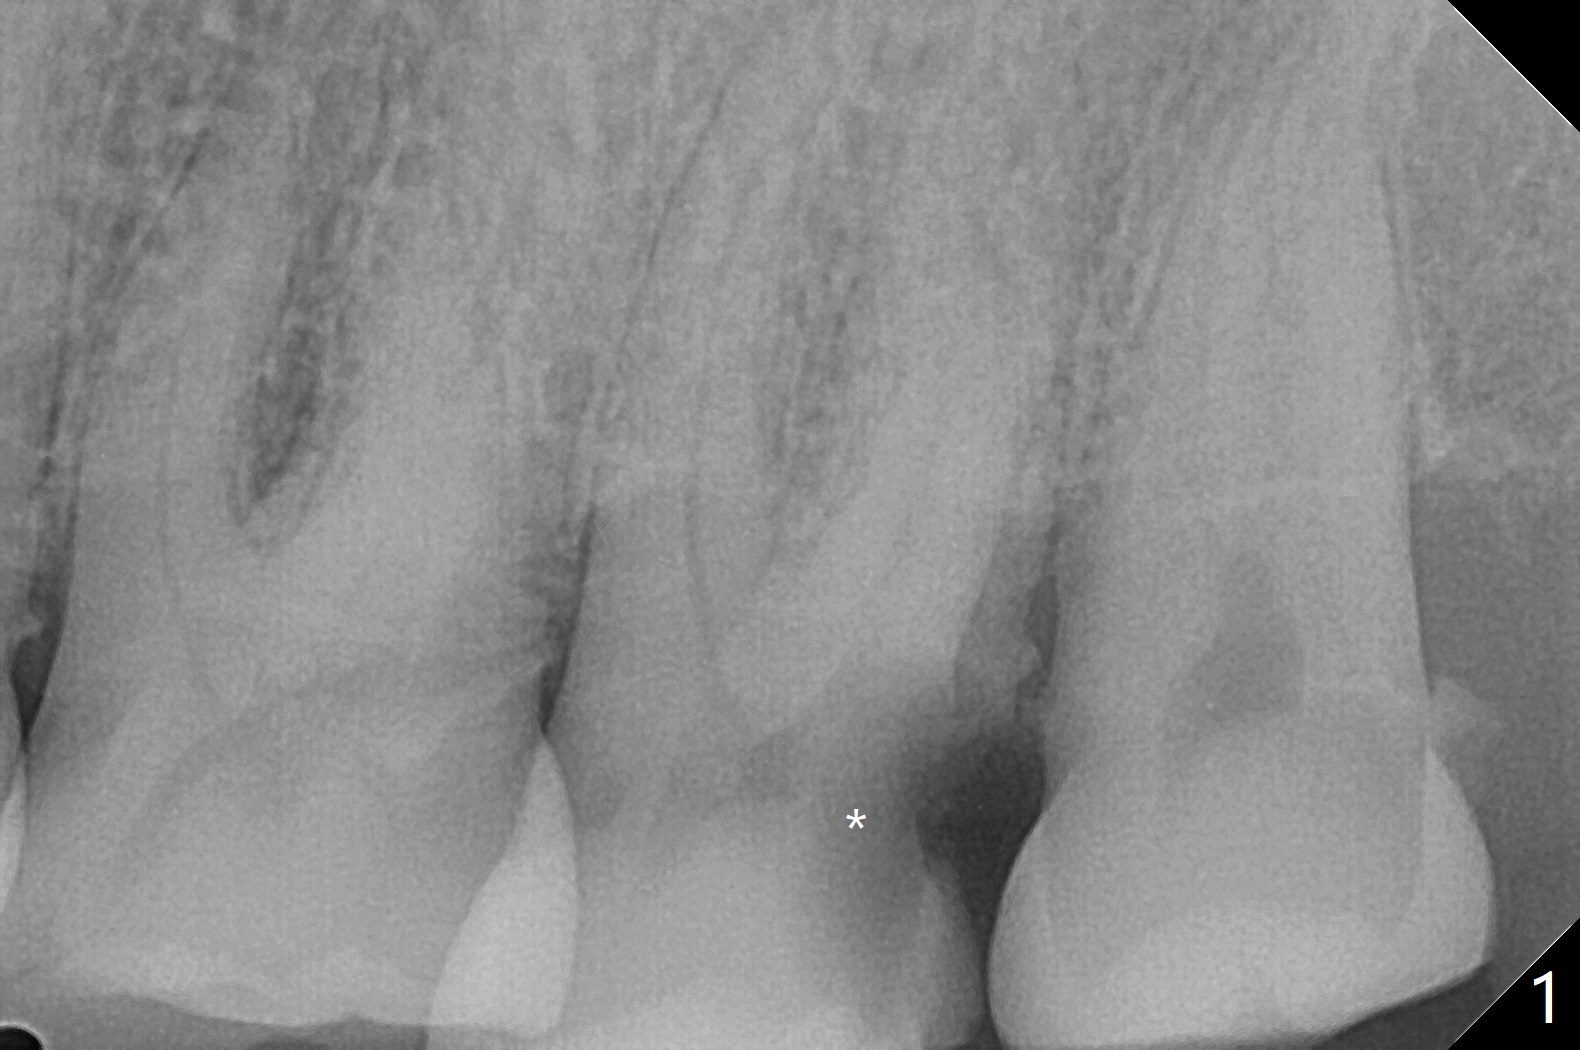

61岁女,胃病,不愿意保留左上7(图一),其实拔牙困难,牙齿小,牙钳显得大,无法旋转,摇把,最后不得不切断,分根拔除,没有肉芽组织或者骨板缺损。由于星期六病人多,使用GEM21S(~.25cc)与皮质骨(图二),Teflon,牙周胶水,牙周敷料固定骨粉。